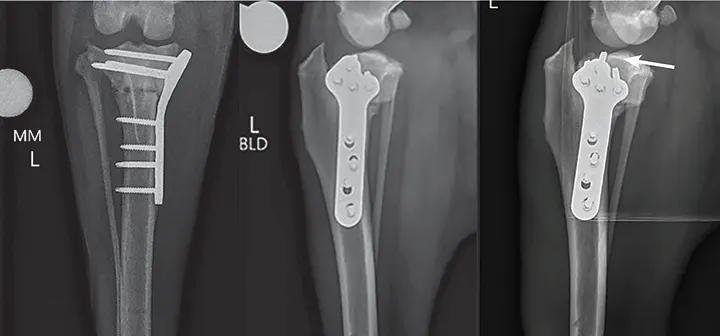

Radiographs from a 7-year-old spayed golden retriever presented with recurrent lameness 3 months after TPLO. A moderate weight-bearing lameness and pain on palpation of the cranial stifle/patellar tendon was identified on examination of the operated limb. Radiographs revealed thickening of the patellar tendon (solid arrows) and an apical patellar fracture (dashed arrow). Lameness resolved with rest, NSAID therapy, and shockwave therapy.